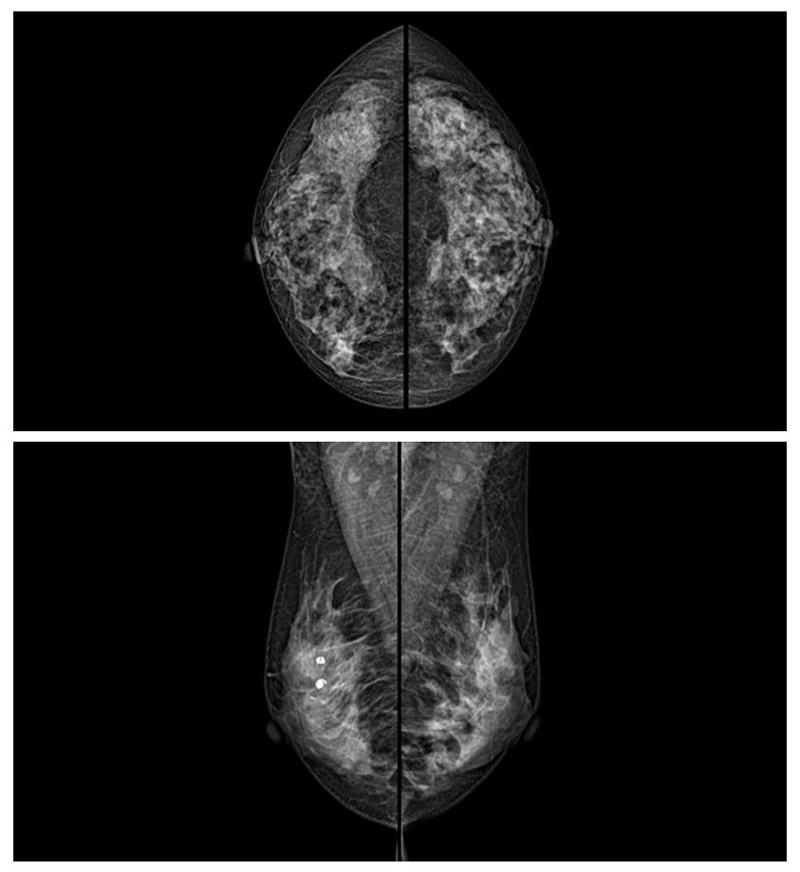

乳腺癌的发生率越来越高,已经是我们国家的癌症之一已成为女性健康“头号杀手”。乳腺DR可提高乳腺癌早期检出率并精准定位。发现和诊断早期乳腺癌最有效的方法之一,明显利大于弊女性都要重视乳腺的检查。辐射很小最简便、最可靠、无创性检查手段,做一次乳腺DR的剂量相当于7周的正常生活。尤其是对于40岁以上的女性尤为重要,那么乳腺DR是怎么进行检查的呢?我们来了解一下,为广大朋友在检查前有点心理准备。检查时候是避开经期的前后,月经来后的7天左右比较合适。需要脱衣服检查,根据拍片的摆位要求,有头尾位置,内外斜位,还有侧位。定点放大压迫方法可以更细微清晰的检查出病灶。

对乳房进行按压,这样才能得到检查的好效果,按压大概60秒左右,做好心理准备不可以过度紧张有点疼痛感觉,这样不会抖动影响了检查的效果。减少患者压迫时间和辐射剂量。可达到最高极限分辨率10.1 lp/mm,可实现高清成像,提高微小病变检出率。可以发现乳腺增生,各种良恶性肿廇通过三维断层扫描,提高乳腺微小癌灶的检出率和早期乳腺疾病特别是乳腺癌的诊断率。通过特殊的支架,加大胶片与物体之间的距离来获取更多的影像信息。